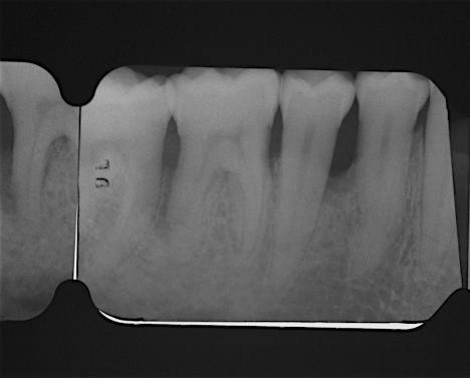

03/22 - Pre-operative radiograph. Deep intrabony defect visible on the distal aspect of tooth 46.

Deep intrabony defects treated using Straumann® Emdogain® - Dr. M. Stefanini